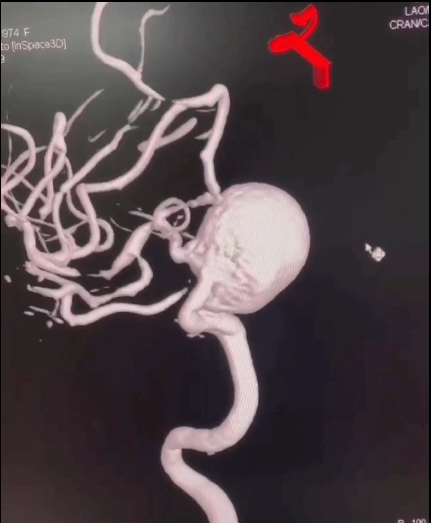

患者以视力模糊主诉入院。诊断颅内大动脉瘤。

动脉瘤3D重建